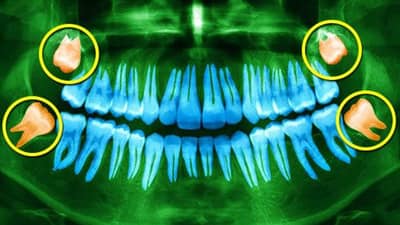

તેથી એ વાત સ્પષ્ટ છે કે ડહાપણના દાંત હોવાનો અર્થ બુદ્ધિ વધી જવી એવો બિલકુલ નથી. પુખ્ત વયના લોકોએ તેની કાળજી લેવી પડશે કારણ કે તે દાંતના છેલ્લા ભાગમાં છે. તેથી, જો આ ભાગમાં સહેજ પણ સમસ્યા હોય તો, તેની સીધી અસર પીડાના સ્વરૂપમાં અનુભવાય છે.